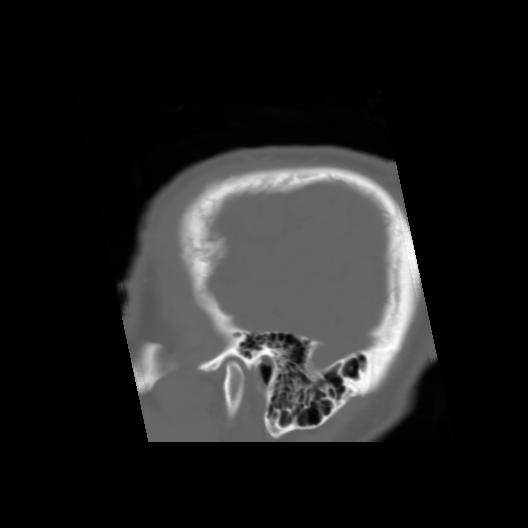

6 CEREBRO,,Sagittal,3.000,CEREBRO,Sagittal,